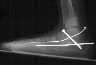

Some mechanism has to be used to correct the hindfoot valgus.. That was the case in this child in which subtalar arthrodesis with autograft bone graft and screw fixation was performed.